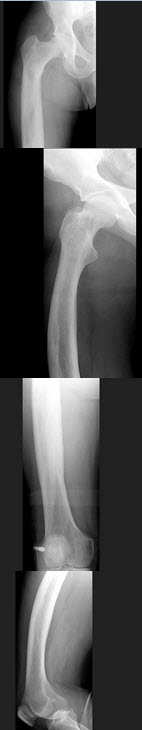

79、单项选择题

男,67岁,右侧股骨痛,结合图像,最可能的诊断是()

A.骨纤维结构不良

B.维生素D缺乏病

C.成骨不全

D.软骨发育不全

E.畸形性骨炎